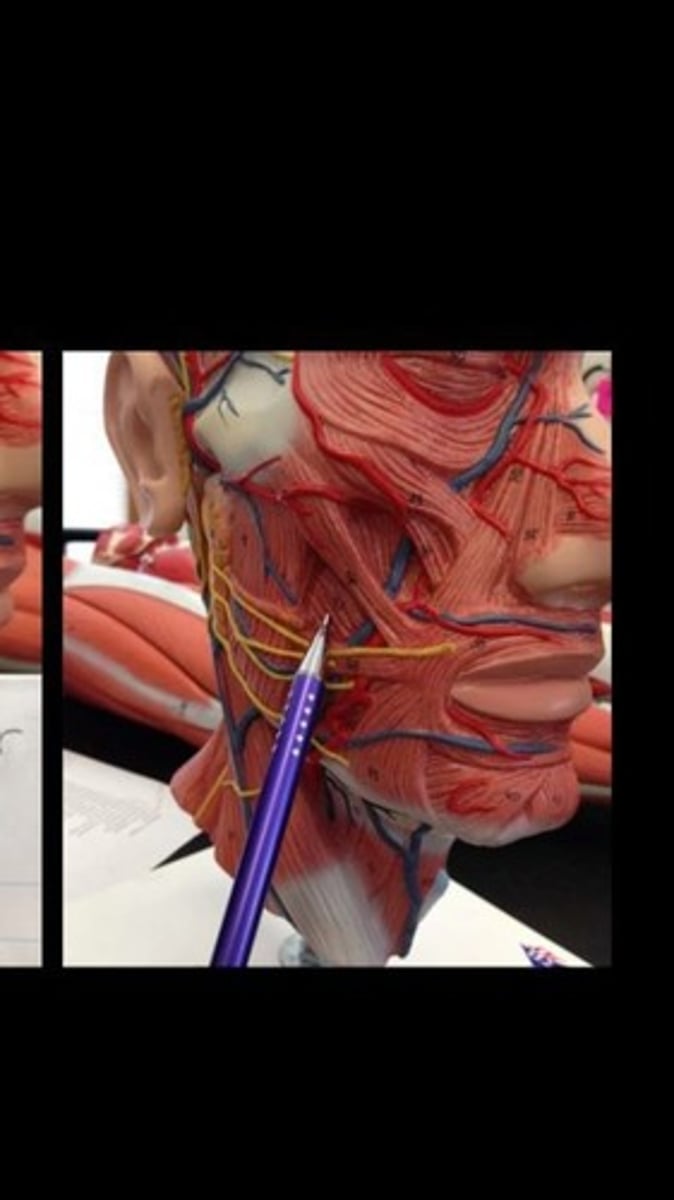

Buccinator

Masseter

Sternocleidomastoid